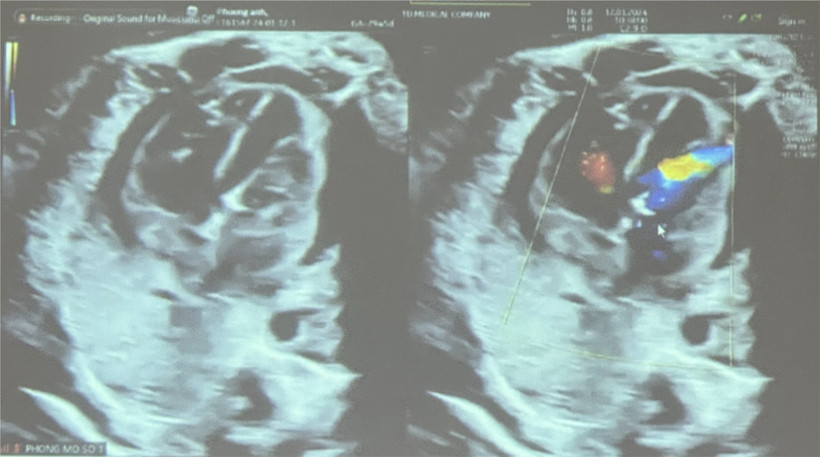

Siêu âm sau can thiệp tim mạch bào thai. (Ảnh: Đinh Hằng/TTXVN)

Đến ngày 11/1, khi thai được 29 tuần, các bác sĩ phát hiện diễn tiến hẹp van động mạch chủ của bào thai trở nặng, đường kính van 2,6 mm, vận tốc máu qua van động mạch chủ 300cm/s, gây thiểu sản thất trái nặng hơn, trào ngược van 2 lá mức độ nặng.

Sau nong, các thông số tuần hoàn của tim bào thai tiến triển tốt, nhịp tim thai 188 lần/phút, có tràn dịch màng ngoài tim nhẹ 4,5mm.

Sản phụ được theo dõi tại phòng mổ 15 phút sau đó và tình trạng tràn dịch màng ngoài tim thai dần ổn định. Đến 13 giờ ngày 12/1, tình trạng tràn dịch màng ngoài tim thai được kiểm soát tốt, nhịp tim thai bình thường, tình trạng sản phụ ổn định.